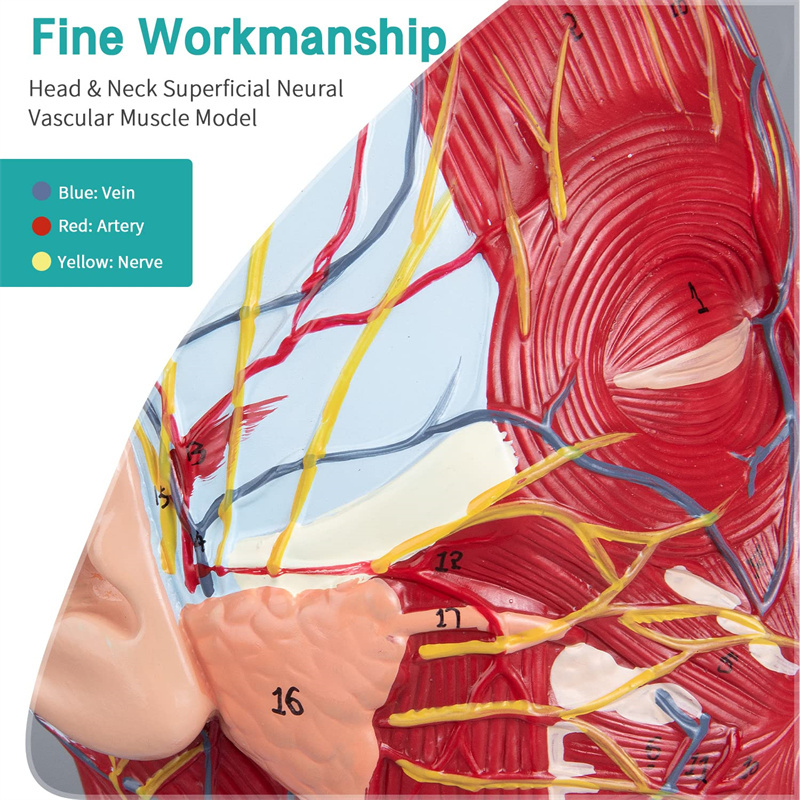

【Model de mușchi neurovascular superficial】 extrem de detaliat, numere marcate, detașabile, adânciți înțelegerea mușchilor superficiali, vaselor, nervilor și structurilor interne ale capului și gâtului. Red-Artery, vene albastru, galben-port.

【Caracteristici】 arată mușchii superficiali ai feței expuse; vasele de sânge superficiale și nervii feței & scalp; structurile interioare ale glandei parotide și ale tractului respirator superior; Structura de secțiune sagitală a coloanei vertebrale cervicale.

Acest model este un model natural de mușchi neurovascular superficial al capului și gâtului, 1 componentă, care arată detaliile capului drept și gâtului drept și secțiunea sagitală mediană, inclusiv mușchii superficiali expuși ai feței, vasele superficiale ale feței și scalpului, nervii și structura medială a glandei parotide și a tractului respirator superior și a structurii secțiunii sagitale a coloanei vertebrale cervicale